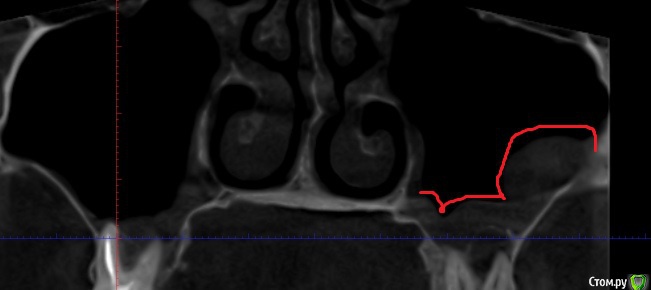

klemento Опубликовано 30 сентября, 2019 Поделиться Опубликовано 30 сентября, 2019 (изменено) Здравствуйте. Прощу помощи, т.е. совета. Проблемы слева вверху. После лечения 6 зуба и дальнейшего его протезирования вкладкой и коронкой - появилась боль при накусывании в области 5-6 зуба. Появляется преимущественно после жевания и попадания пищи. Знакомый посоветовал сделать КТ. Я обратился в 3 клиники. В 1 мне сказали удалить 6 и 7, т.к. что-то пошло в пазуху(снимок пазухи), там видно в виде пятна серого, а так же на 4 и 5 делать резекцию, т.к. выведен материал за верхушку. В двух других - сказали попытаться вскрыть 7 зуб, т.к. не понятно, что там с ним - может и получиться спасти, а 6 - не трогать(мол как простоит так простоит) . Про 5 ничего сказать не могут. Так же на 4 что-то есть и про него ничего не сказали.Хотелось бы понять как поступить. Возможно ли сохранить 7 зуб и действительно ли не трогать 6, но тогда ходить с воспалением? На одном из снимков есть двойка протезированная - на ней воспаление уже несколько лет и не беспокоит - трогать ее или делать резекцию? Понимаю, что дурак раз запустил так зубы, но обидно, что много денег отдал на 6 зуб и теперь под удаление его... Хотелось бы услышать какие-то варианты. Заранее спасибо. Изменено 30 сентября, 2019 пользователем klemento Ссылка на комментарий

DmitrySH Опубликовано 30 сентября, 2019 Поделиться Опубликовано 30 сентября, 2019 Те изменения в пазухе, которые вы показали на снимке, вряд ли можно отнести к зубам. Воспаление вокруг корня зуба 27 можно вполне успешно лечить, это не проблема. Вопрос в том, что сам зуб достаточно сильно разрушен и состоит из большой пломбы. Тоже самое касается и зуба 26. В такой ситуации нужен очный осмотр и решении о целесообразности сохранения/удаления с учетом дальнейшего ортопедического восстановления Ссылка на комментарий

krokomot Опубликовано 3 октября, 2019 Поделиться Опубликовано 3 октября, 2019 Вот КТ. Только надо вручную ссылку копировать, а то из форума не открывает.https://dropmefiles.com/1aSGrА что делать с воспалением под запротезированном зубом? Врачи снимать коронку и вкладу не хотят браться.Томограмма отвратительная, то что по ней удалось определить что в 7м не запломбирован дистальный канал, лечение перепломбировка, нужен еще прицельный снимок коронок 6-ого и 7ого, из-за наводок невозможно определить состояние тканей вокруг этих коронок и особенно в промежутке между 6-м и 7-м, в 5м выведения материала нет, в 4-м есть 0.5 мм это не критично никакие резекции делать не нужно, по поводу 2-ки лечите канал и переставляйте коронку. для обьективной картины нужна хорошая томограмма на современном томографе типа Sirona, и прицельные снимки 5-й,6-й,7-й зубы на визиографе с позиционером, а не пальцем датчик держать. Скорее всего все зубы спасабельны, но это не точно)) Ссылка на комментарий